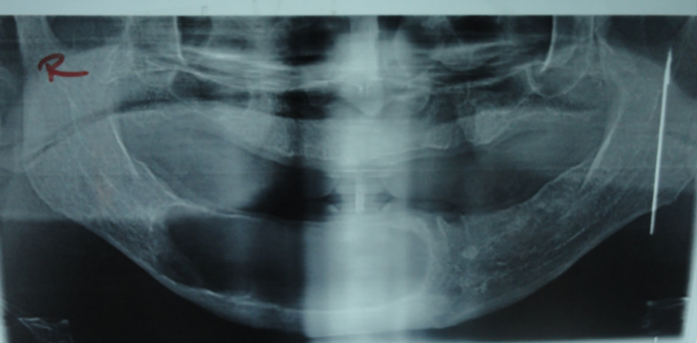

Cholesterol granuloma is a rare clinical entity described as inflammatory granulation in response to the deposit of cholesterol crystals. It can develop in any portion of air cells within the temporal bone as a result of a lack of aeration and adequate drainage. Here, we report a 65-year-old edentulous male with a painless slight expansion on the lower right body of the mandible, with a history of previous multiple lower denture constructions. A panoramic radiograph showed a well-defined unilocular radiolucency on the right body region of the mandibular bone. An incisional biopsy was done, then the lesion was completely enucleated surgically with packing, and the final diagnosis was confirmed by a histopathological examination report.